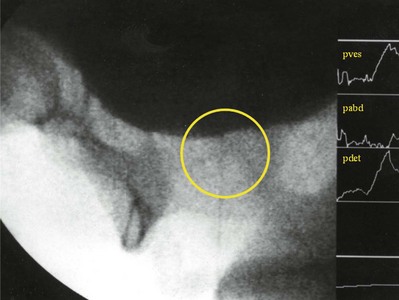

The measurement of compliance can be affected by a number of factors. Sometimes an increase in Pdet during cystometry is seen as a result of rapid filling (filling during cystometry is almost always faster than physiologic filling). This is more of an accommodation problem rather than a true decrease in compliance. When Pdet is seen to be rising, filling may be stopped or reduced to see if the effect is real. An IDC, particularly if it is of sustained and low amplitude, can be confused with impaired compliance. If filling is stopped and the pressure returns to baseline, then the compliance is not impaired. Finally, a number of “pop-off” mechanisms can make compliance seem better than it actually is. Vesicoureteral reflux and bladder diverticulum are two examples. With reflux, pressure is actually transferred to the refluxing renal unit and may be harmful. The author has seen instances where the upper tract holds more urine than the bladder. VUDS (see later) is useful in these cases. Because a bladder diverticulum is actually part of the bladder, it may provide a protective effect for the upper tracts. Finally, an incompetent outlet may be a pop-off mechanism. This may only become apparent when outlet resistance is increased, which can be done during cystometry by occluding the outlet but may not be seen until the outlet resistance is surgically increased (e.g., with an artificial urinary sphincter or sling procedure).

VUDS consists of the simultaneous measurement of UDS parameters and imaging of the lower urinary tract. It provides the most precise evaluation of voiding function and dysfunction and is particularly useful when anatomic structure and function are important (Keane at al, 1993; McGuire et al, 1996). Examples of where VUDS are useful include the localization of obstruction, detecting incontinence not seen on physical examination, and evaluating vesicoureteral reflux during storage and/or voiding. It can be particularly useful in cases of neuropathic voiding dysfunction. VUDS is the only way to evaluate bladder neck dysfunction and can confirm sphincteric dysfunction diagnosed by EMG. Also, there are instances where a known anatomic abnormality exists and simultaneous imaging can determine if that abnormality is playing a role in voiding dysfunction (e.g., bladder or urethral diverticulum, vesicoureteral reflux).